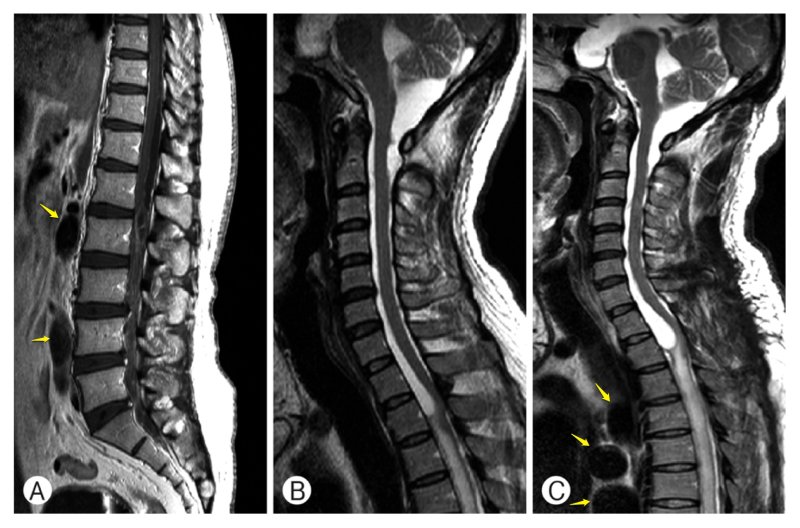

Спинальный нейроцистицеркоз. Стрелки указывают на цисты. Han Joo Lee, Moo Sung Kang, Kyung Hyun Kim. Intradural Spinal Cysticercosis: Case Series. The Nerve 2015; 1(1): 20-25.